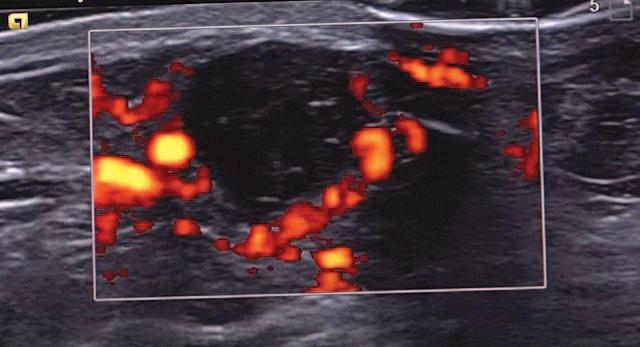

Paint Estes Pink was started 10 years ago for local businesses to participate during Rodeo Week to raise awareness of the town’s needs and funding for oncology services at Estes Park Health. This year’s Estes Park Health Foundation campaign is focused on adding a Philips EPIQ Elite ultrasound machine to EPH services. This technology will allow oncology services to perform precise, image-guided needle biopsies, increasing the overall speed and accuracy of cancer diagnosis and care for residents of Estes Park.